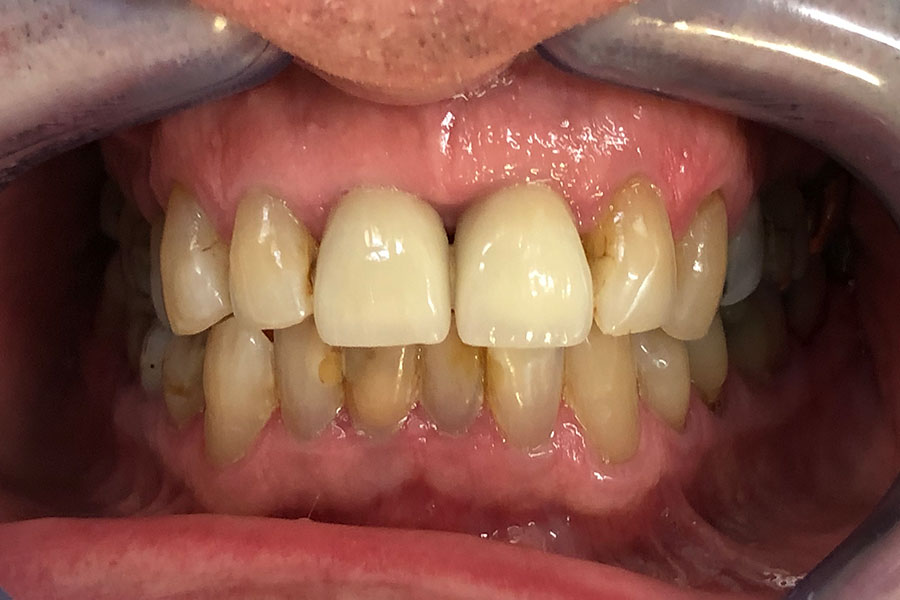

Nic lost two front teeth while playing football about 40 years ago.

He wore a removable metal partial denture. These teeth were finally restored with two dental implants to support the teeth individually.